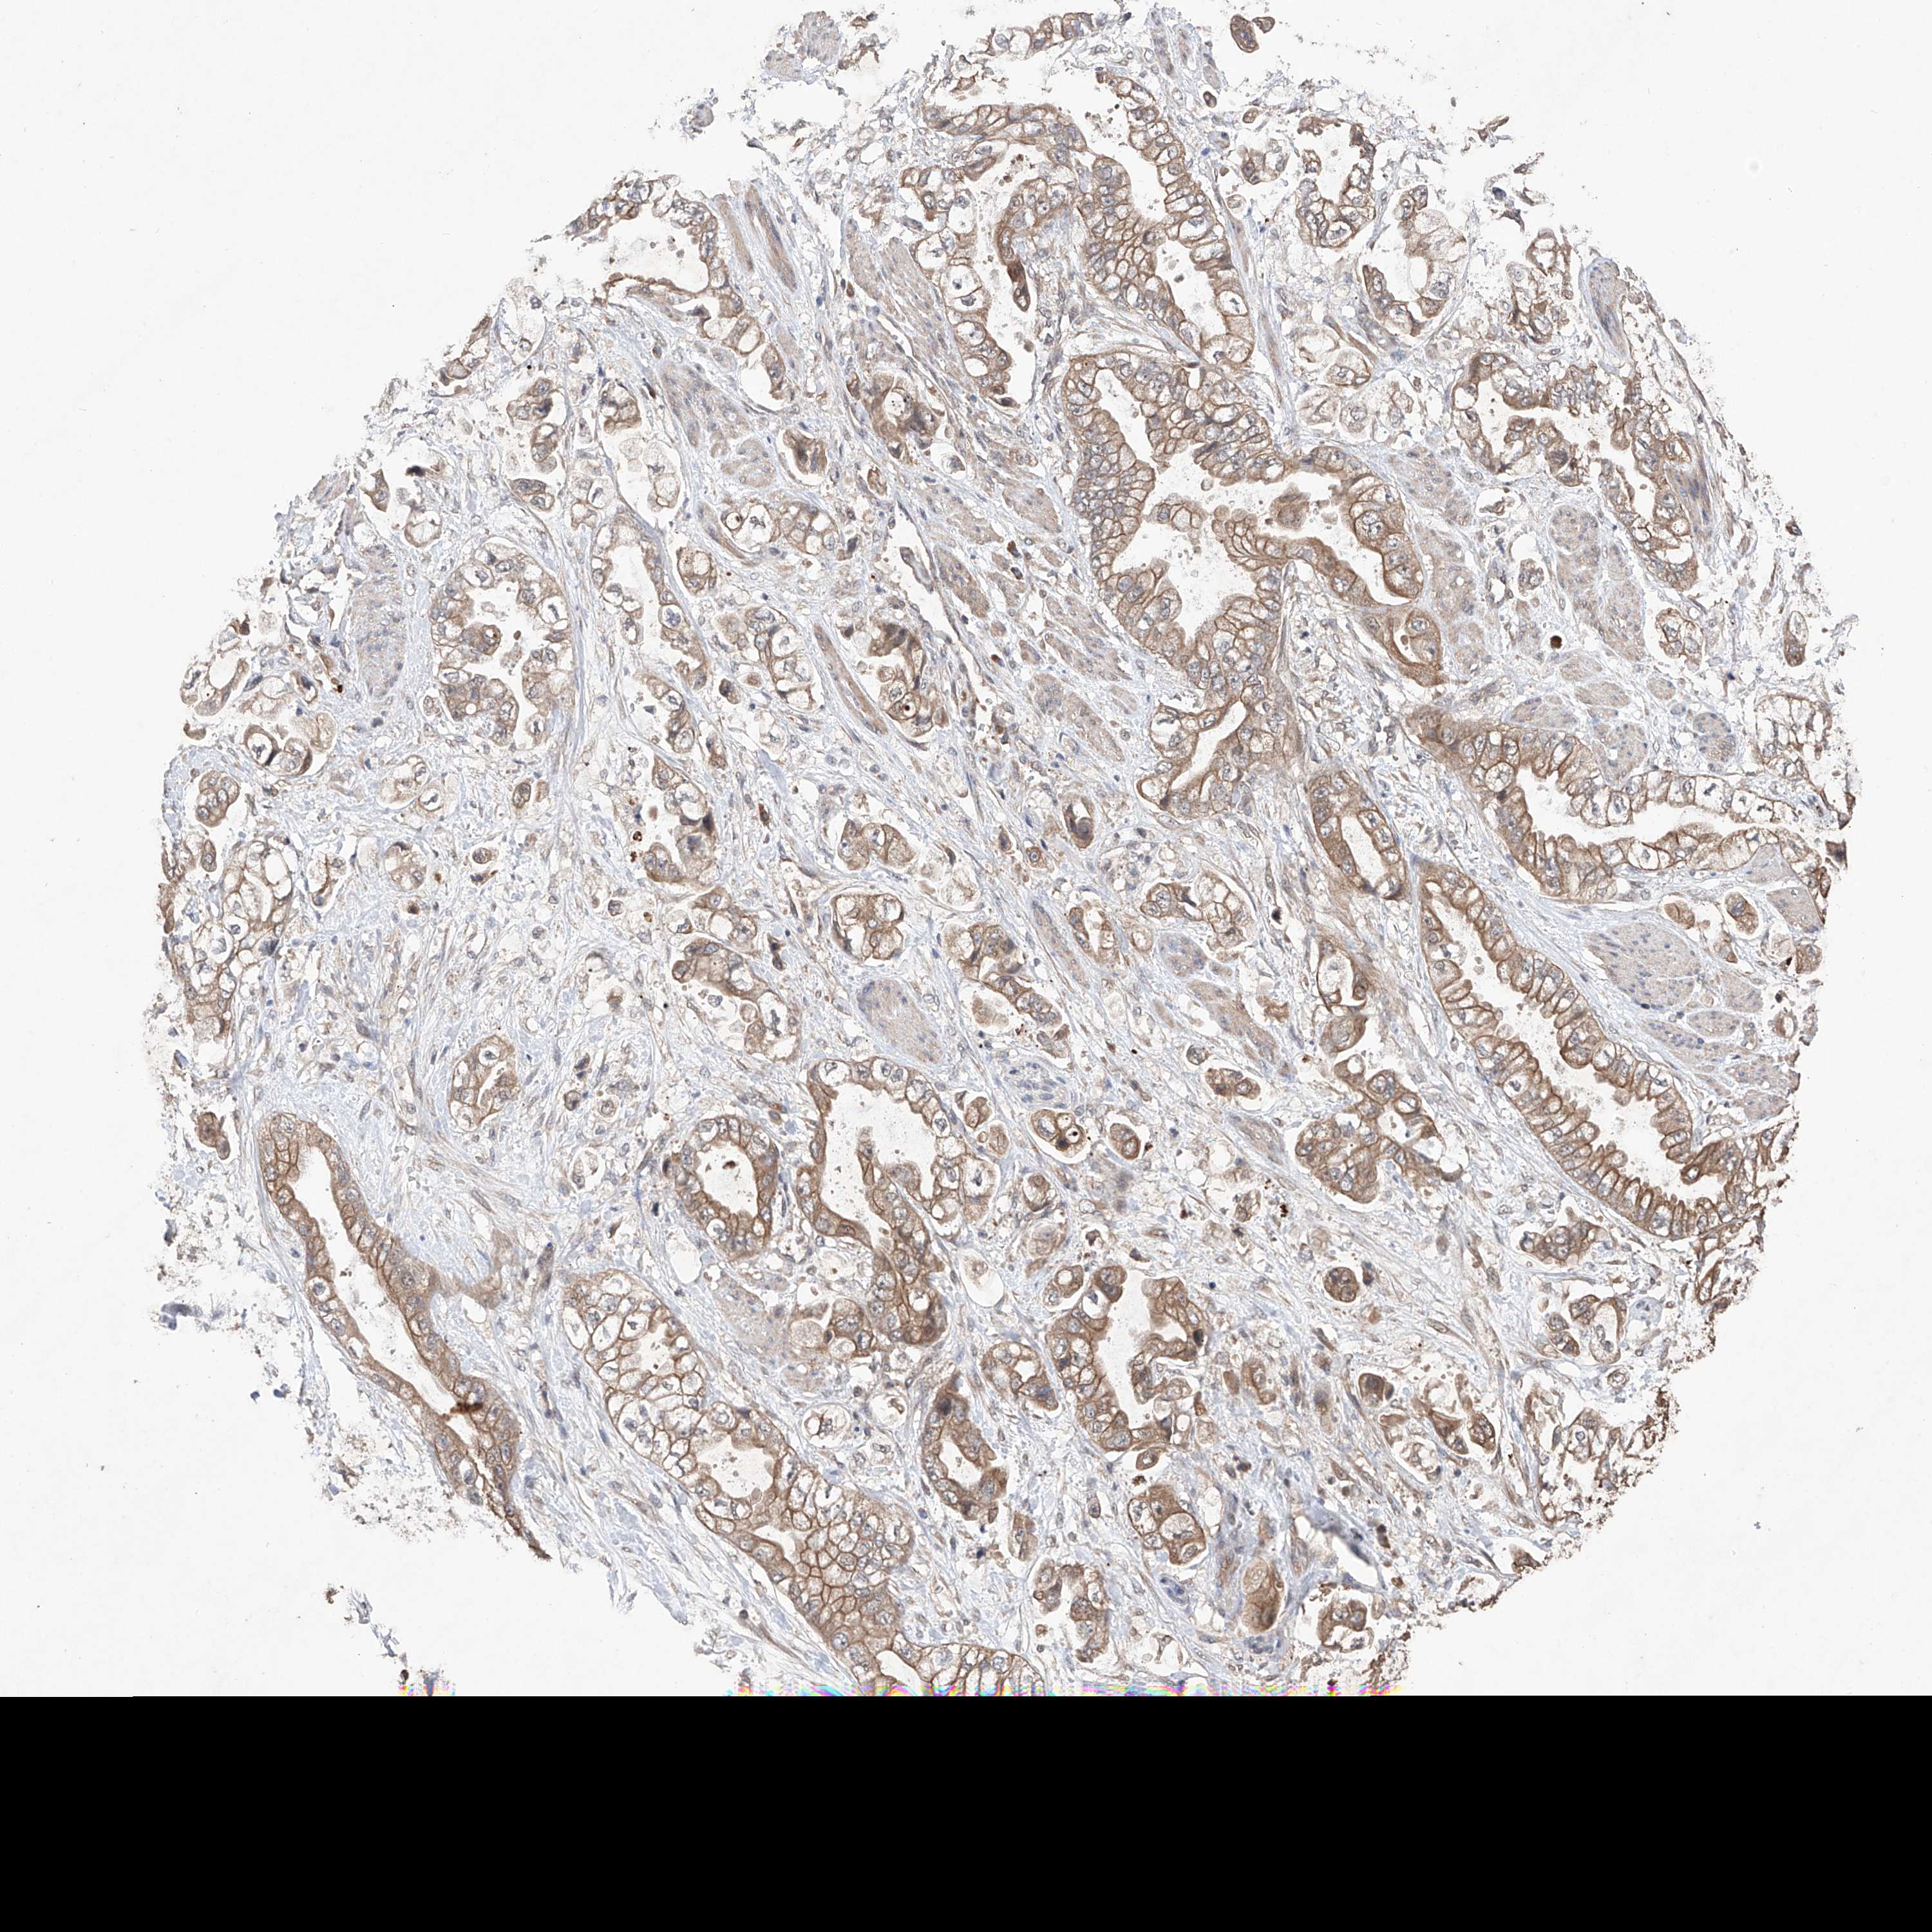

STOMACH CANCER - Protein expressioni

A mouse-over function shows sample information and annotation data. Click on an image to view it in a full screen mode. Samples can be filtered based on level of antibody staining by selecting one or several of the following categories: high, medium, low and not detected. The assay and annotation is described here.

Note that samples used for immunohistochemistry by the Human Protein Atlas do not correspond to samples in the TCGA dataset.

Antibody stainingi

Antibody staining in the annotated cell types in the current human tissue is reported as not detected, low, medium, or high, based on conventional immunohistochemistry profiling in selected tissues. This score is based on the combination of the staining intensity and fraction of stained cells.

Each image is clickable and will lead to virtual microscopy that enables deeper exploration of all samples and also displays staining intensity scores, fraction scores and subcellular localization as well as patient and tissue information for each sample.

Antibody HPA030060

Antibody HPA030061

Staining

High

Medium

Low

Not detected

Intensity

Strong

Moderate

Weak

Negative

Quantity

>75%

75%-25%

<25%

None

Location

Nuclear

Cytoplasmic/membranous

Cytoplasmic/membranous,nuclear

Adenocarcinoma, NOS